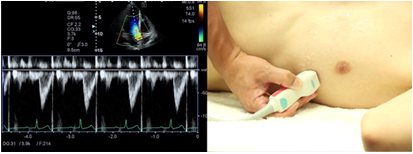

Right ventricular ejection flow pattern

To obtain the right ventricular ejection flow pattern, visualize the longitudinal view of the right ventricular outflow tract and set the position of the sample volume at the center of the right ventricular outflow tract just below the pulmonary valve. The right ventricular ejection flow pattern is used for measurement of the maximum flow rate, the time velocity integrated value, the acceleration time (AcT), and ejection time (ET).